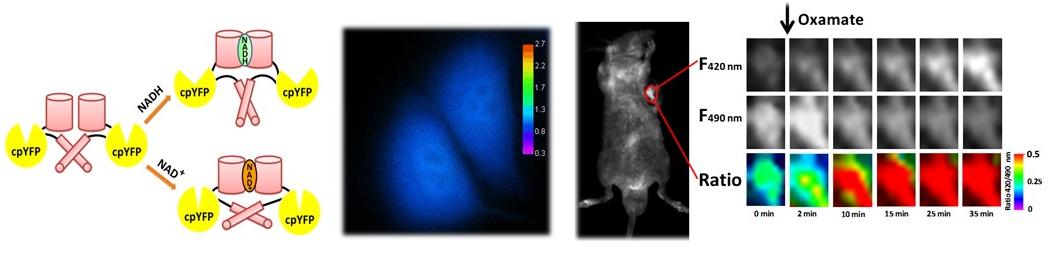

SoNar探针可实现活细胞与活体动物中对不同类型细胞代谢表型的动态监测与成像,以及细胞代谢相关的活性化合物的高通量筛选。我们发现了肿瘤干细胞特殊的代谢模式,也发现了一些显著改变细胞代谢抗癌药物。(Cell Metabolism 2015, 21, 777; Nature Protocols, 2016, 11, 1345; Cell Metabolism 2019, 29, 950;Blood 2020, 136, 553)